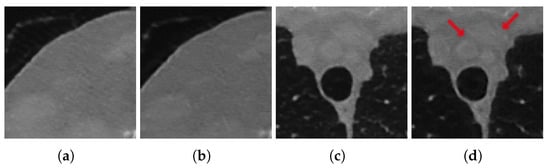

As anticipated, the advent of deep learning is revolutionizing how researchers address CT (and, in particular, SpCT) image reconstruction, and a number of works have already been published trying to exploit the deep learning data-adaptivity for reaching high-quality medical images [,]. To this aim, we now focus on the paradigm sometimes referred to as Learned Post-Processing (LPP) or Deep Artifact Correction, which employs deep neural networks to suppress artefacts on roughly reconstructed images. This framework is graphically represented in Figure 2 for the specific context of SpCT, where the FBP algorithm is typically used to transform the subsampled sinogram data into the 2D medical image, and the LPP is performed at the end of whole reconstruction workflow to remove streaking artefacts and noise.

Figure 2. Graphical draft of the considered two-step workflow for tomographic reconstruction from sparse-view data.